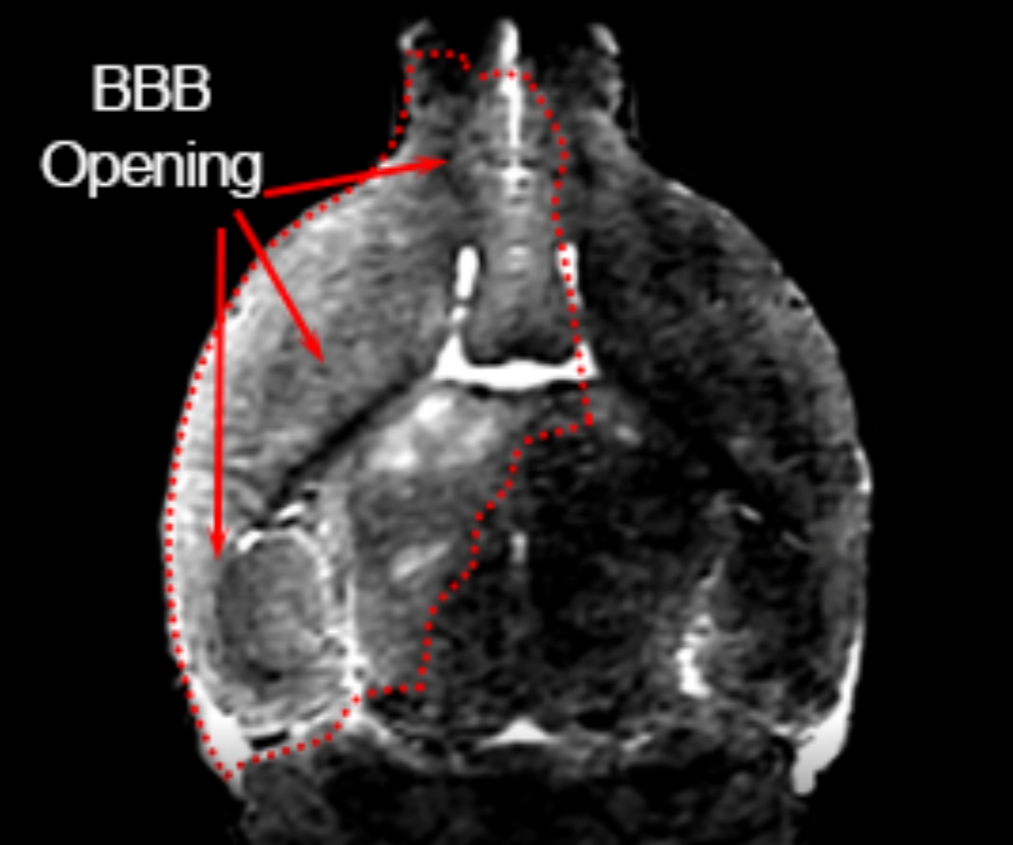

Frontiers Microenvironmental Variations After BloodBrain Barrier